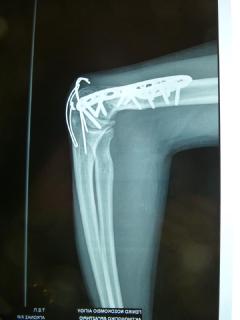

4 χρόνια μετά το χειρουργείο